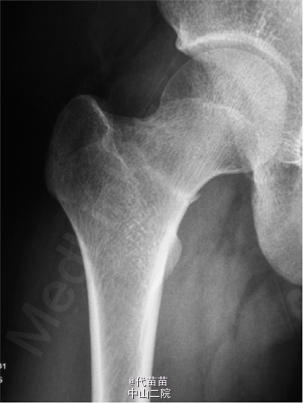

患者男 , 17 岁 , 战士。因右髋部疼痛逐渐加重 1 个月来诊。患者于 2013 年 9 月入伍后开始训练 , 1 个月后无明显诱因出现右髋部疼痛 , 行走及训练时加重 , 休息后能缓解 , 无低热、盗汗 , 无昼轻夜重等现象 , 曾到师医院就诊 , 给予对症治疗 , 后疼痛症状逐渐加重。影响活动 , 不能坚持训练来本院就诊并入院。查体 :一般状况良好 , 心肺腹无异常。右髋部及腹股沟区皮肤无红肿 , 皮温不高 , 无静脉显露 , 右髋后上方压痛 , 无放散 , 右髋部叩击痛阳性 , 右髋关节活动尚好 , 活动时疼痛加重 , 未触及明确包块。血、尿、便化验检查无异常 , 血清碱性磷酸酶 126 U/L。X 线片示 :右股骨颈基底断裂 , 无明显移位 , 局部骨痂形成 ( 见图 1)。诊断:右股骨颈疲劳骨折。入院后完善检查及术前准备, 2 d 后给予行小切口三枚空心螺钉内固定术 ( 见图 2)。术后对症治疗,半个月后拄拐不负重行功能锻炼, 出院后 3 个月复查 X 线片示 :右股骨颈基底部骨小梁及骨皮质连续 , 骨折线消失 , 达到骨性愈合。 应力性骨折又称疲劳性骨折 , 常发生在运动员及新兵训练中 , 此类人员频繁的超负荷训练致骨每天承受反复负荷,以致骨发生局部微损伤 , 如果这种损伤不断积累 , 超过机体修复能力 , 就会产生骨的疲劳性骨折。此类患者往往无明确的外伤史 , 但有大运动量的病史 , 尤其是军人及运动员不能忽视 , 多数患者患侧髋后上部及臀后部疼痛 , 活动时加重 , 休息后缓解 , 部分患者随着病情发展 , 停止运动或休息后仍不能使疼痛缓解 , 查体时 , 患髋后上方及臀部有压痛 ,局部偶有肿胀 , 大粗隆处叩击痛阳性。辅助检查 :DR 及 CR一般可在 1 个月内出现骨膜反应征象 , 大约 3 个月左右由于骨折修复 , 可见有骨痂形成 , 但无法与相关疾病做出鉴别诊断 , CT 的高分辨率扫描 , 能清晰显示骨折线及骨膜增生 , 对平片不能早期确认的病例有较高的诊断价值 , 螺旋 CT 的三维重建可根据需要对高度怀疑的骨组织任意面及任何位置进行重建 , 以此可发现较细的骨折线 , 尤其对于股骨颈及坐骨支等解剖结构复杂区域的疲劳性骨折较适用。MR 其多方位多平面成像 , 敏感性优于 X 线片 , 特别是能早期显示骨折线 ,以及骨折周围软组织 , 髓腔内的水肿和出血。对那些X线片或 CT 扫描有疑问的疲劳骨折病例 , MR 有显著的早期诊断和鉴别诊断价值。 疲劳骨折治疗原则是早发现 , 早治疗 , 可限制原有运动 , 休息为主 , 对极少不稳定或移位的骨折 , 可采取手术固定。此外 , 在训练中 , 应科学施教 , 劳逸结合 , 因每个人的不同体质针对性的制定出训练计划 , 避免同一部位频繁、多次训练。如在训练中出现下肢某部位进行性疼痛 , 应及时来医院诊。